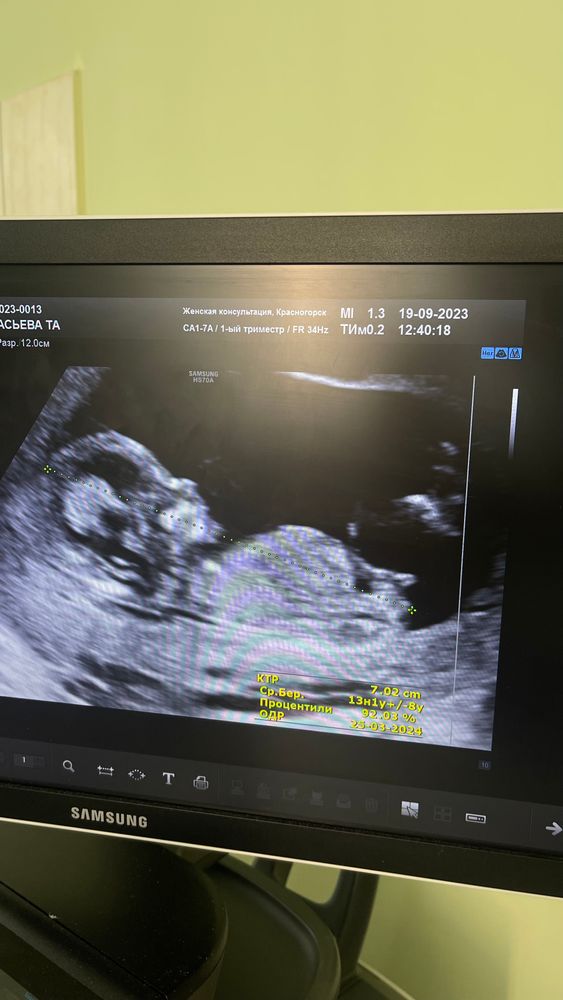

Как мне узистка сказала « если вниз смотрит то девочка , если вверх то мальчик « а вам что сказали ? Сделайте тест на определение пола по крови. Он 100% поавильный

Мила, я НИПТ сдала , жду результат. Там будет пол 100%) сейчас просто интересно, раз уж узист выдвинула предположения) я вообще не просила ее, она в самом конце вдруг сообщила, что вероятно девочка, хотя вначале говорила, что пол непонятен.

Узи Моска Пол ребёнка